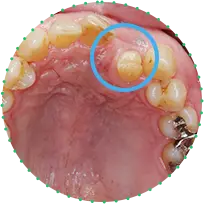

Before

After

主訴

上の前歯が抜けそう

治療期間

6か月

治療費

30万円

治療内容

右上1番を抜歯後に骨と歯茎を増やし、隣の歯の裏側を少量削り、接着性ブリッジにて修復

治療のリスク

咬み合わせによっては、セラミックが欠ける可能性があります。